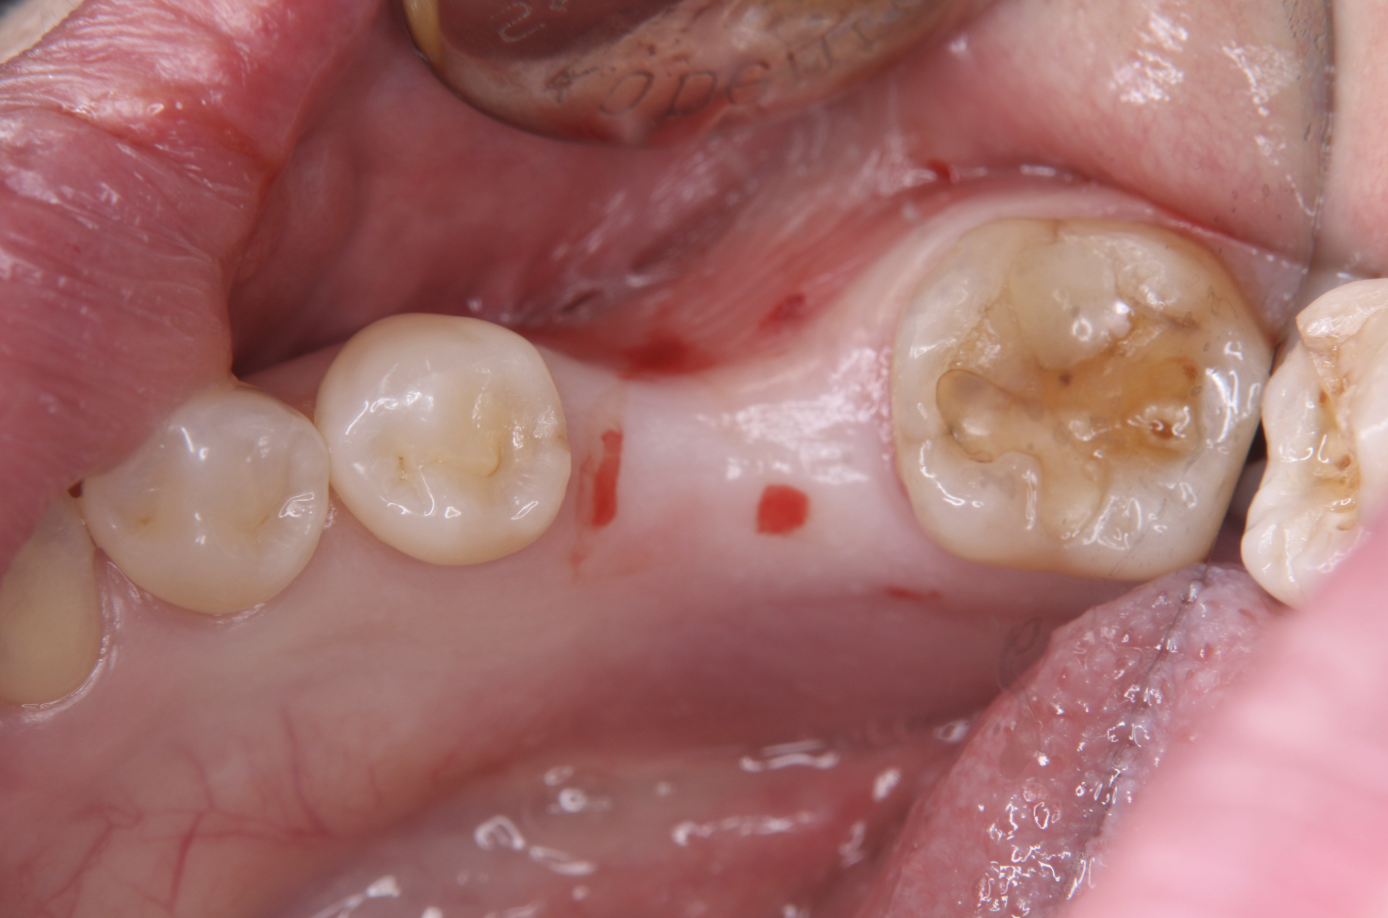

前回の続きとして、ここからはいよいよ実際の移植処置に入っていきます。

今回の症例では、再生療法を併用した歯牙移植を行っています。

まずは、事前に採取しておいた自家骨を形成済みの移植床へ丁寧に填入していきます。